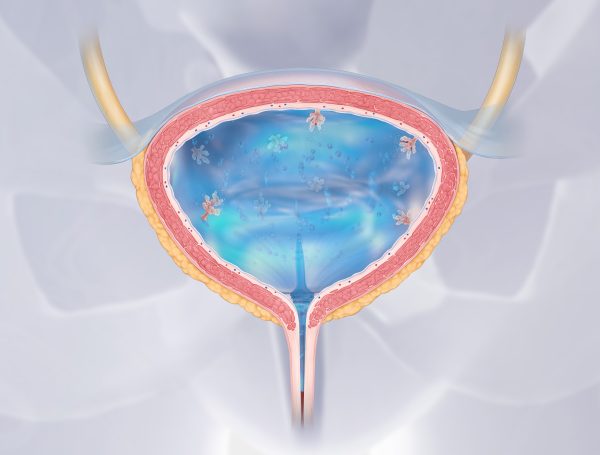

Mesane kanseri cinsel yolla bulaşır mı sorusu, gerek mesane kanseri olan hastalar gerekse ve mesane kanseri olan hastaların eşleri tarafından çok merak edilen konular arasında yer alır. Mesane kanseri, en